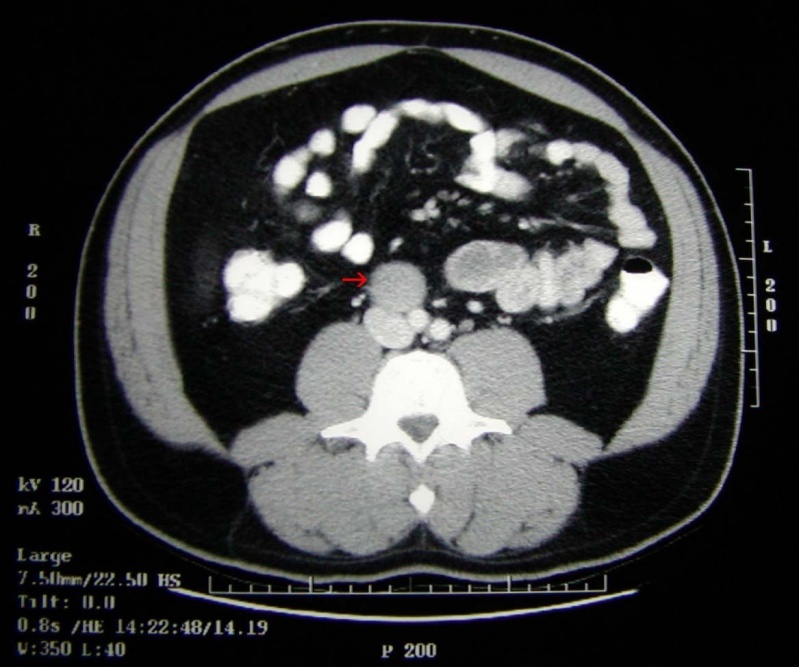

Exame de Imagem de Tomografia do Abdome Total

Medicom ExamesCom um exame de imagem é possível o médico analisar e ver o interior do corpo do paciente, para que desta maneira seja possível dar um diagnóstico para o paciente. O exame de imagem é diferente de...

Exame de Imagem de Tomografia do Abdome Total

Exame de Imagem de Tomografia do Abdome Total

Exame de Imagem de Tomografia do Abdome Total

Medicom ExamesCom um exame de imagem é possível o médico analisar e ver o interior do corpo do paciente, para que desta maneira seja possível dar um diagnóstico... Cotar Agora Saiba Mais